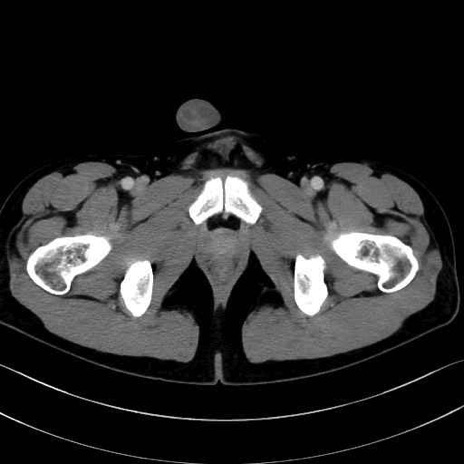

5. 大腿前面(大腿四頭筋群・伸筋群)

縫工筋 (Sartorius)

大腿直筋 (Rectus femoris)

外側広筋 (Vastus lateralis)

中間広筋 (Vastus intermedius)

6. 大腿内側(内転筋群)

恥骨筋 (Pectineus)

長内転筋 (Adductor longus)

短内転筋 (Adductor brevis)

大内転筋・小内転筋 (Adductor magnus / Adductor minimus)